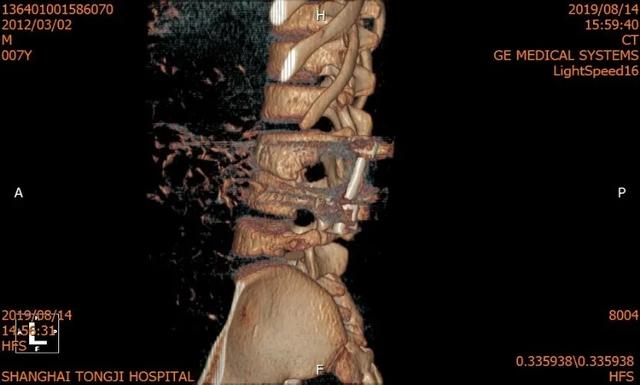

医疗团队本着对少年儿童的关爱,把担子压在自己肩上,准备得仔细又仔细。术前还以患者畸形脊柱的超薄 CT 为基础,运用最先进的 3D 打印技术构建了患者脊柱模型,并利用数字模拟技术模拟了患者内固定的最佳植入路径,反复模拟手术,做好了充分的术前准备。

术前 CT & 3D 打印